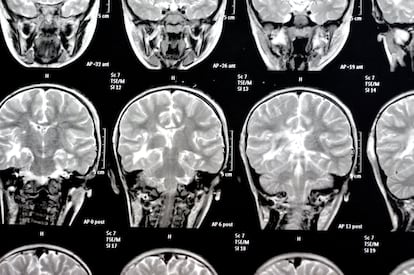

Ranganath es pionero en el uso de resonancias magnéticas para estudiar cómo recordamos eventos pasados. Y ha comprobado que lo hacemos de forma cambiante. Nuestro presente modifica de alguna forma cómo leemos nuestro pasado. “Cada vez que recordamos un evento, lo vemos desde nuestra perspectiva actual”, señala. “Así, por ejemplo, si recordaras una ruptura reciente, la evocarías de manera muy diferente a si la recordaras muchos años después. El mismo recuerdo de un evento traumático puede presentarse como una historia de supervivencia y coraje”, señala.

Kepa Paz-Alonso es líder del grupo de investigación Lenguaje y Memoria en el Basque Center on Cognition. Lleva años utilizando la resonancia magnética para ver cómo y dónde se ilumina el cerebro cuando la gente está recordando. Por eso explica: “Si recuperas muchas veces una vivencia, esta se queda cristalizada en el cerebro. Cuando esto sucede, se establece una nueva sinapsis. Y eso es el inicio de una memoria”. La sinapsis es el proceso de comunicación entre las neuronas; es el impulso nervioso por el cual los neurotransmisores saltan de una neurona a otra transportando cierta información.